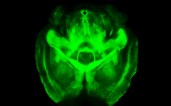

Ou talvez não. Karl Deisseroth e os seus colegas desenvolveram um gel sintético transparente que impede a desintegração, na ausência dos lípidos, do tecido cerebral. Retiraram os lípidos e os cérebros assim tratados de ratinhos ficaram intactos – e transparentes.

Quanto à nova técnica, permitiu obter imagens ao microscópio com uma resolução sem precedente de cérebros inteiros. E testes realizados num cérebro humano conservado no formol permitem esperar que o método também possa servir para pôr esse nosso mais complexo órgão “a nu”, para estudar o seu funcionamento e as suas doenças.

Os cientistas substituíram portanto os lípidos do cérebro por um gel inicialmente líquido. Coloca-se o cérebro de molho na solução e passados uns tempos aquece-se ligeiramente. O gel solidifica – e como não se liga aos lípidos, estes podem então ser evacuados rapidamente por electroforese (técnica que permite a separação das moléculas graças a um campo eléctrico). “O que resta”, diz o mesmo comunicado, “é um cérebro 3D transparente com todas as suas estruturas importantes – neurónios, axónios e dendrites [as extensões dos neurónios], sinapses [os pontos de passagem do impulso nervoso entre neurónios], proteínas, ácidos nucleicos [o material genético] e por aí fora – intactos e cada um no seu lugar.”

Mas as vantagens não acabam aí: como o gel é poroso, a técnica (já agora, Clarity é o acrónimo de clear lipid-exchanged anatomically rigid imaging/immunostaining-compatible tissue hydrogel) também torna o órgão “gelificado” permeável às substâncias químicas. Os cientistas demonstraram assim, em ratinhos, que é possível introduzir anticorpos para tornar fluorescentes estruturas cerebrais específicas. E mais: esses anticorpos também podem ser facilmente retirados, deixando o órgão pronto para novos testes – uma operação que pode ser repetida múltiplas vezes.